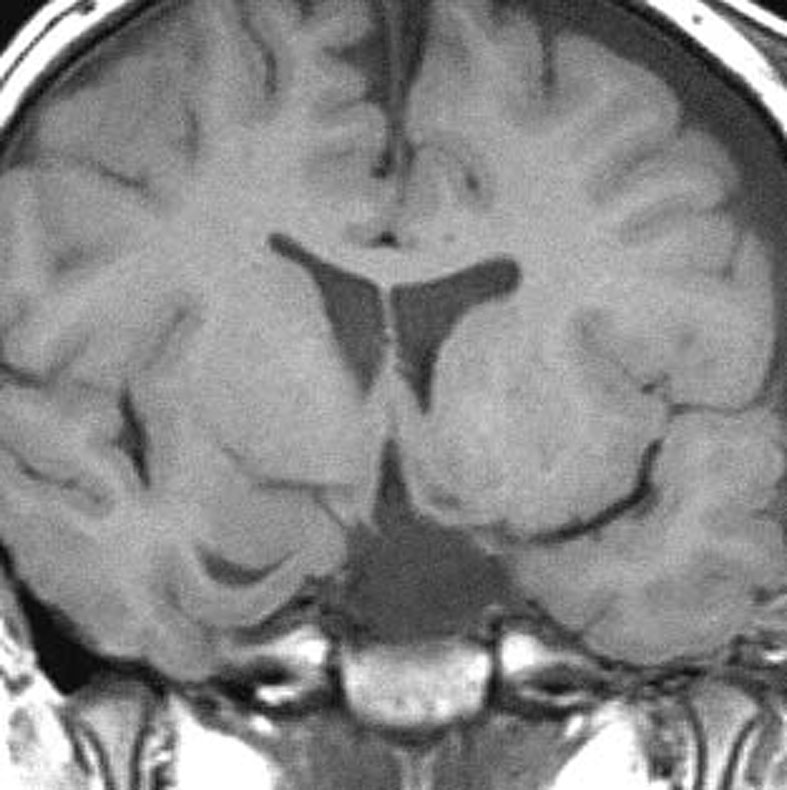

2歳でgelastic seizureを発症,6歳で思春期早発となりました

左視床下部に限局して柄を有するものです,左視索と乳頭体との境界はありません

おそらく左視床下部の機能低下と難治性の発作が原因で,左大脳半球の萎縮(あるいは発達不良)が認められます